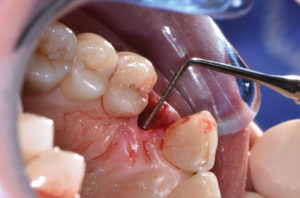

Nel mese di febbraio 2018 si procede all’inserimento di un impianto Max Stability 3,75×12 mm, disegnando un lembo anticipato palatino per consentire un aumento dei tessuti vestibolari. Si sutura con tecnica roll-flap, trasformando l’elemento parziale mobile in una corona singola a carico immediato sul moncone temporaneo con l’applicazione dei concetti protesici BOPT (Biologically Oriented Preparation Technique) (Figg. 31-43).

- Fig. 31

- Fig. 32

- Fig. 33

- Fig. 34

- Fig. 35

- Fig. 36

- Fig. 37

- Fig. 38

- Fig. 39

- Fig. 40

- Fig. 41

- Fig. 42

- Fig. 43